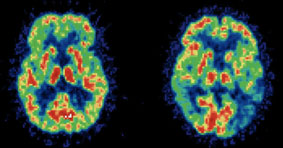

Rất nhiều quyển sách y học xem bộ não giống như bất kỳ cơ quan nào khác trong cơ thể. Để cải thiện trí não, họ khuyên chúng ta nên có một chế độ ăn uống cân bằng, ngủ đủ giấc, nên tránh các chất độc hại như cồn (từ bia, rượu) hoặc nicotine (thuốc lá). Đây có thể được xem là những lời khuyên hữu ích, nhưng theo Tiến sĩ Rudolph Tanzi đến từ Trường Y Harvard, muốn cải thiện trí não chúng ta phải hiểu được những đặc trưng của não.

Não là cơ quan duy nhất thay đổi ngay lập tức dựa trên cách suy nghĩ của con người, theo hướng tích cực hay tiêu cực (các cơ quan khác cũng thay đổi nhưng chậm hơn do phải trải qua trung tâm điều khiển là não bộ). Tùy vào sự lựa chọn của chúng ta khi suy nghĩ, các tế bào não, các dây thần kinh và các khu vực não sẽ thay đổi nhiều hay ít. Nói cách khác, suy nghĩ một cách tích cực là cách hữu hiệu nhất giúp cải thiện trí não.